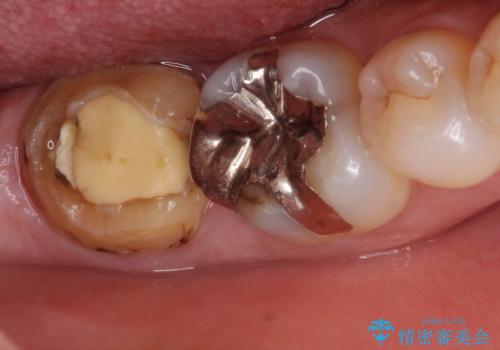

唾液から歯を守るため、ラバーダムシートを装着し古い材料を全て除去したうえで、う蝕を取り治療しました。

レントゲン写真から古い詰め物が神経と近接している事がわかります。万一に備え、ラバーダムシートを装着しながら治療を行いました。(万が一、虫歯の除去中に神経が露出した場合、神経を唾液から守るため。)

その後、新しい土台を立て、仮歯に置き換えたのち、フルジルコニアクラウンにて治療を行いました。